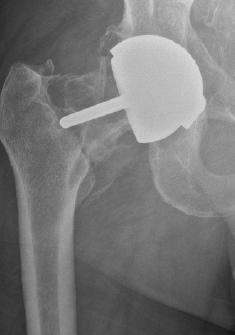

Resultat: De nya ytersättningsproteserna introducerades av främst McMinn och Amstutz strax efter sekelskiftet 2000 och fick ett betydande genomslag, inte minst som protes för unga och aktiva ”idrottsprotes” (bild till höger). Rapporter om komplikationer med höga nivåer av metalljoner, destruerande

mjukvävnad runt leden (pseudotumör) och collumfrakturer började dock relativt snart påverka entusiasmen.

En av tillverkarna drog 2010 in sin protes med omedelbar verkan. Men nästan 100 000 patienter hade då redan blivit opererade med denna protes. Härefter har metoden snabbt minskat i användning – även om vissa ”entusiaster” fortsätter att genomföra operationen. De vetenskapligt verifierade riskerna med ytersättningsprotes är;

1. Avaskulär nekros av collum/caput (bild). Detta kan leda till fraktur på lårbenshalsen.

Röntgen av osteolys, caputnekros och collumfraktur samt en ytersättningsprotes infälld i bild.

2. Pseudotumör – som i vissa fall kan bli mycket stor och destruera benet runt leden. Pseudotumör har kopplats till ökade koncentrationer av metalljoner i vävnaden kring protesen och i blodet. Pseudotumörer kan förekomma både hos patienter som erhållit ytersättningsprotes och sådana som opererats med andra helproteser med stort metallhuvud kombinerat ledskål i metall.

3. Höga nivåer av cirkulerande metalljoner (krom och kobolt) från ledens ytor.

Genom hårt driven marknadsföring främst via nätet träffar vi tyvärr fortfarande på patienter som är nyopererade med ytersättningsproteser – ofta i Belgien eller Holland – och som snabbt har drabbats av komplikationer. I allt för många fall har unga patienter drabbats av alvarliga och helt onödiga komplikationer. Patienter med metall mot metall-leder behöver dessutom följas avseende nivåer av metalljoner och utveckling av pseudotumör – vilket är mycket kostsamt och helt onödigt eftersom det finns betydligt säkrare alternativ.

PET-CT av ytersättningsprotes 1 vecka, 4 månader och 14 månader efter operationen. Pilarna visar en gradvis utveckling av caputnekros i den opererade höften. Gösta Ullmark, Gävle.